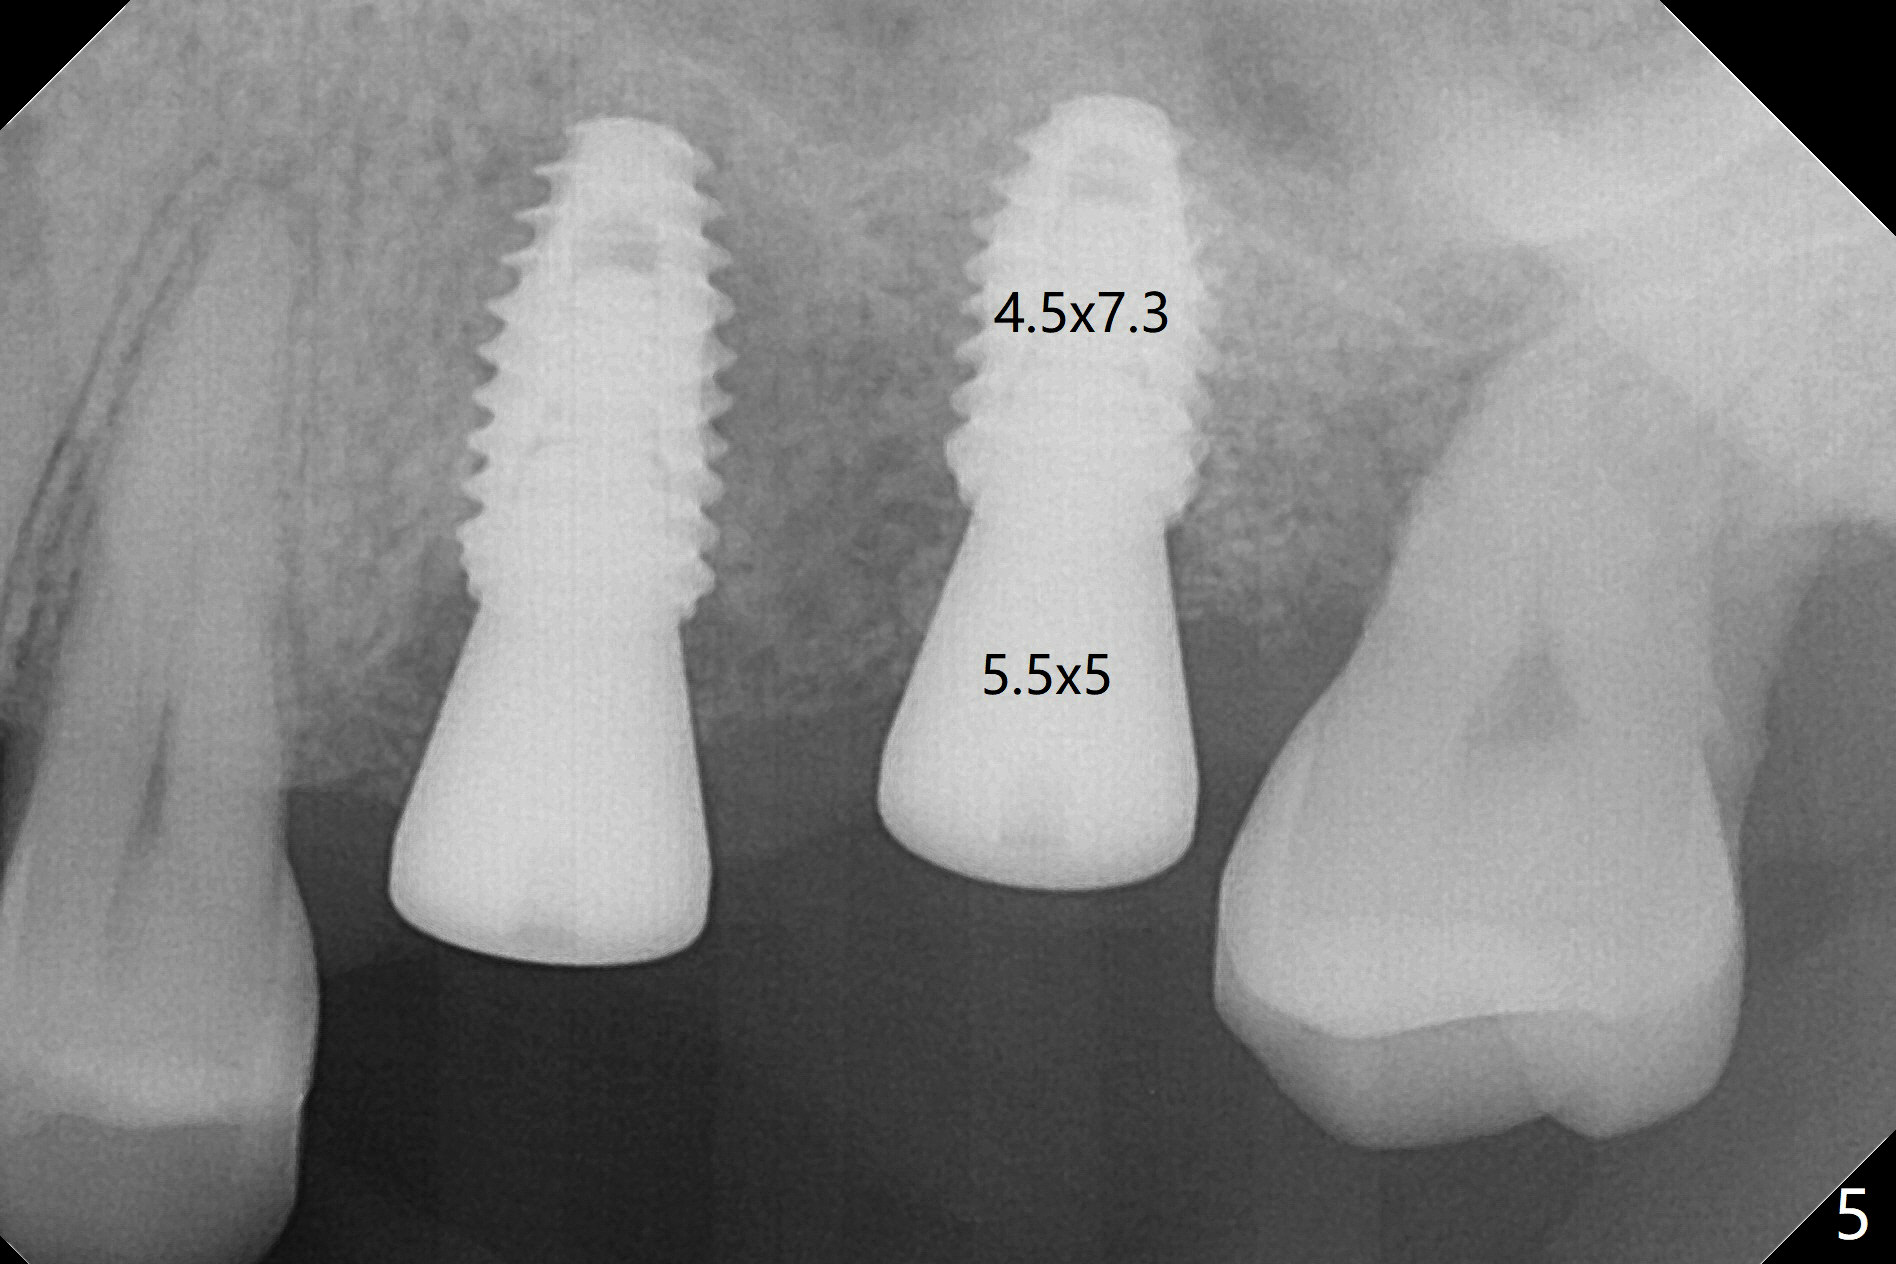

Four and a half months post implant removal, the patient returns for #14 implant placement. To increase bone density, bone expanders are used through the metal sleeve of the previous guide after use of 2.2x7.5 mm drill with 3 O-rings (1 mm shorter than previously designed; Fig.1). The osteotomy continues to form by bone expanders until 2.4/3.7 mm, followed by a 4x10 mm dummy implant (Fig.2-4). Finally a 4.5x7.3 mm implant is placed with ~ 25 Ncm with simultaneous sinus lift (Fig.5). There is no postop nasal hemorrhage. The implant dislodges with the healing abutment 2 months postop. The patient will return for follow up 3 months post 2nd loss. We are going to try again with PRF, UF guided sinus lift kit, sinus expander kit. After implant placement, use the implant at #13 and abutments at #13 and 14 to fabricate splinted provisional to hole the newly placed implant in place. Take preop PA and possible CT. In fact CT and impression are retaken for a new guide.